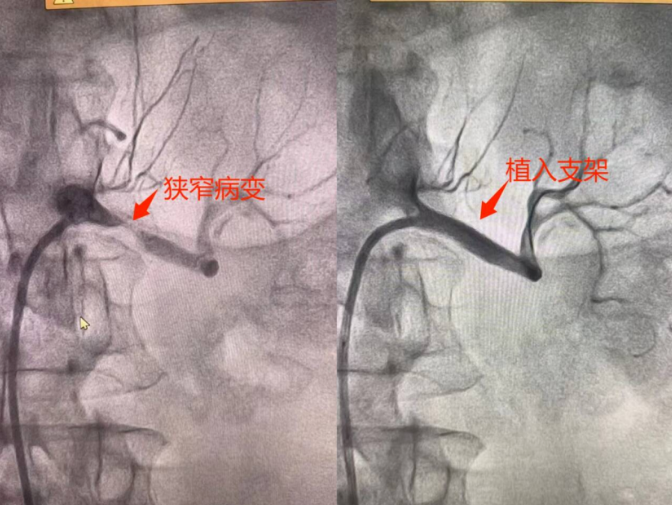

微創(chuàng)介入,立竿見影為有效控制血壓,避免腎功能進一步受損,心血管內(nèi)科團隊為患者制定了詳細的治療方案,行冠狀動脈造影同時行腎動脈造影檢查進一步明確患者冠脈及腎動脈血管情況,根據(jù)冠脈造影結(jié)果給予冠狀動脈支架植入術(shù),根據(jù)腎動脈造影結(jié)果給予患者行左腎動脈支架植入術(shù)。在介入導管室的配合下,手術(shù)團隊通過微創(chuàng)介入技術(shù),成功為患者同時植入了腎動脈支架及冠脈支架,恢復了冠狀動脈及腎動脈的正常血流。術(shù)后,患者血壓迅速下降,胸痛癥狀明顯緩解,術(shù)后血壓穩(wěn)定在正常范圍,患者恢復良好。